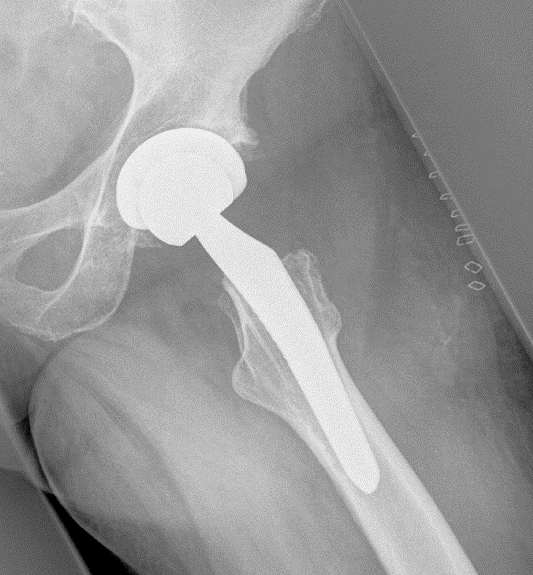

Ist der Verschleiß des Hüftgelenks weit fortgeschritten, kann ein künstlicher Gelenkersatz Beschwerden reduzieren.

Erhärtet sich der Verdacht einer weit fortgeschrittenen Hüftarthrose, wählt der behandelnde Arzt ein für den Patienten geeignetes Implantat aus. Im Cellitinnen-Krankenhaus Maria-Hilf kommt eine Vielzahl an Prothesenarten zum Einsatz, die an die individuellen Faktoren angepasst sind. Alle Auswahlmöglichkeiten werden in der Regel minimal-invasiv durch die AMIS-Operationstechnik eingesetzt. Das bedeutet, dass Muskeln und Sehnen nicht durchtrennt, sondern lediglich beiseitegeschoben werden. Für Patienten hat das den Vorteil, dass sich die Genesungsdauer deutlich verkürzt und kosmetisch unauffällige Narben zurückbleiben. Darüber hinaus lassen sich verschiedene Möglichkeiten der Prothesenverankerung unterscheiden.

Eine zementfreie Prothese kommt besonders für Patienten zwischen 60 und 80 Jahren mit einem gesunden Knochenstoffwechsel in Frage. Dabei werden die beschädigte Hüftpfannen und der Hüftkopf künstlich nachgebildet und mit dem Knochen verpresst. Indem das gesunde Knochengewebe mit der Zeit an die Prothese festwächst, entsteht eine feste und dauerhafte Einheit. Patienten können das Gelenk bereits unmittelbar nach der Operation voll belasten.

Bei der zementierten Prothese kommt ein spezieller, schnell aushärtender Knochenzement zur Anwendung, der das Kunstgelenk mit dem Knochen verbindet. Ein Vorteil dieser Befestigungsart ist, dass sie auch bei schwachem Knochen eine primäre Stabilität bietet. Besonders für Patienten, deren Knochenstruktur Schäden aufweist, beispielsweise durch Osteoporose, ist diese Art der Befestigung geeignet.

Die Hybridprothese bezeichnet eine Kombination aus zementfreiem und zementiertem Implantat. Dabei wird die Gelenkpfanne in der Regel zementfrei fixiert, während der Prothesenschaft mit Zement im Oberschenkelknochen verankert wird.